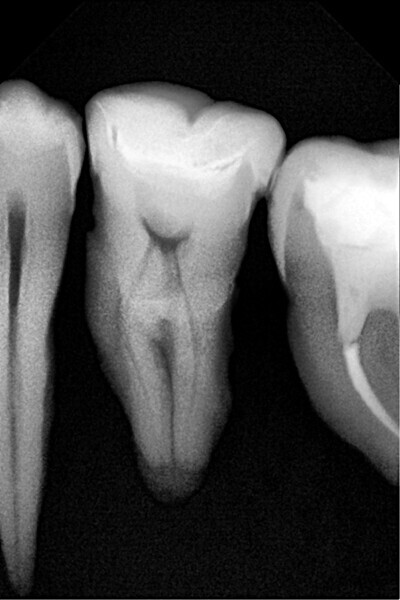

1. functional and aesthetic reconstruction of a maxillary anterior tooth using fibre-reinforced flexible micro-posts after endodontic treatment (Figs. 3–20);

Example 1—showing functional and aesthetic reconstruction of a maxillary anterior tooth using fibre-reinforced flexible micro-posts after endodontic treatment.